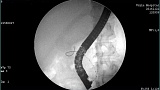

- Атлас